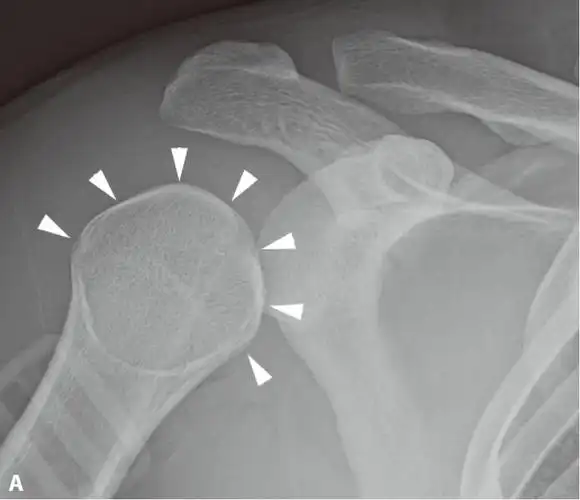

肩关节半脱位

肩关节ap位x线平片显示肱骨头(白箭头)内旋导致的形态变圆("灯泡征").